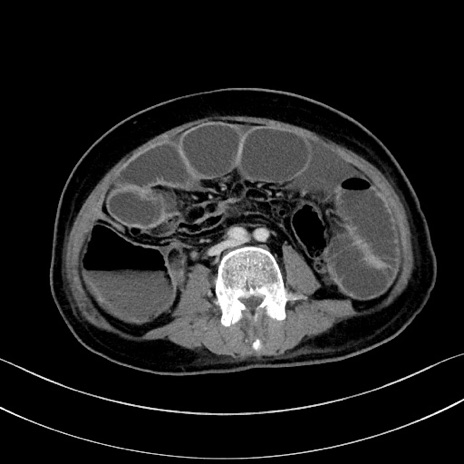

症例28(横断像)

【症例】60歳代男性

【主訴】嘔吐

【現病歴】胃癌にて胃全摘後。食思不振が悪化し、夜中に嘔吐することがある。

【既往歴】胃癌、胃全摘、脾摘、胆摘後

【データ】WBC 5900、CRP 10.56